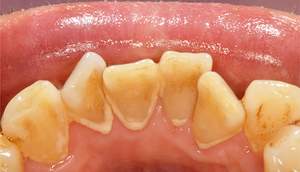

歯石除去

| 年齢 | 56歳・男性 |

|---|---|

| 主訴 | 主訴:歯石除去 治療部位:全顎 |

| 治療内容 | 初診検査・歯石除去 |

| 治療期間 | 60分 |

| 費用 | 合計約5,000円 初診検査約3,000〜4,000円 歯石除去約1,000円 (2024年4月現在) (歯の本数や検査内容で料金が変動します。) |

| リスク・副作用 | ・歯と歯の間に隙間ができるので、息が漏れ発音しにくいと感じることがあります。 ・歯ぐきの炎症がある場合は歯石除去中に出血を伴う可能性があります。 ・処置後に歯がしみることがあります。 ・歯ぐきの炎症が軽減すると歯ぐきが引き締まり、歯が長く見えることがあります。 |

| 治療方針 | 歯石除去・ブラッシング指導後SRP(歯ぐきの中に付着する歯石の除去) |

| 特記事項 | ・30年ぶりの歯科医院 ・毎食後の歯ブラシ習慣はあるが1分程度 |

| 担当者所見 | 全体の検査と歯石除去希望で来院されました。 特に下顎前歯部の歯と歯の間の歯石が、笑った時に見えてしまい気になるとのことで、初診検査後に歯石除去を行いました。 ブラッシング指導は歯間ブラシの入れ方と歯ブラシの動かし方をお伝えしました。 今後は治療と共に縁下歯石(歯ぐきの中に付着する歯石)の除去を行なっていく予定です。 |